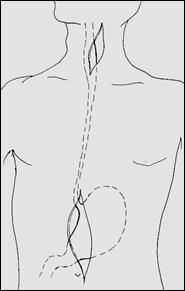

Рис. 7. Схема выкраивания желудочного трансплантата для пластики пищевода по способу Льюиса (1) и схема наложения пищеводно-желудочного внутригрудного анастомоза (2). Схема доступов – на рис 6.

Рис. 8. Схема левого торакоабдоминального доступа к нижнегрудному отделу пищевода и желудку при операции типа Garlock (1) и схема операции (2).

Рис. 9. Схема резекции рубцово измененного пищевода из АЦД с одномоментной пластикой пищевода целым желудком, проведенным через заднее средостение, с анастомозом на шее.